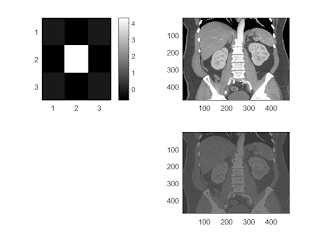

unsharp mask

b = fspecial('unsharp'); subplot(221); imagesc(b); colorbar; subplot(222); imagesc(I); subplot(224); I2 = conv2(I,b,'same'); imagesc(I2);